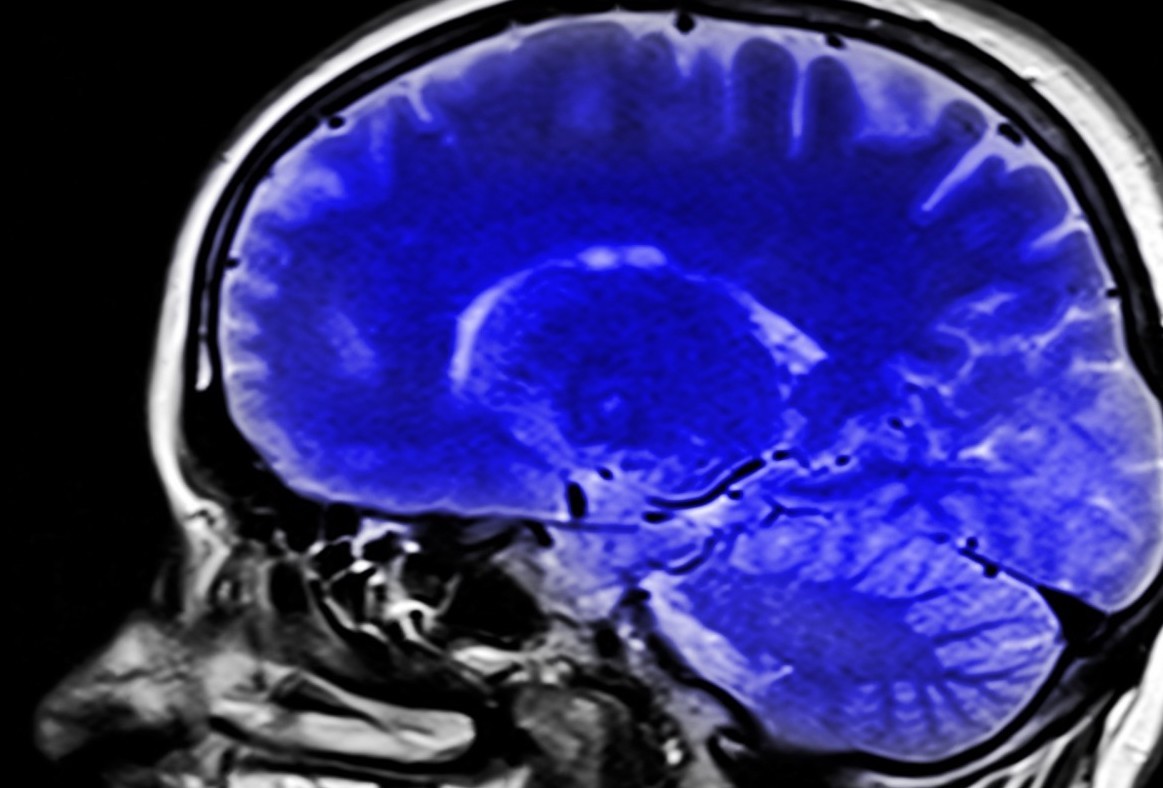

Un estudio realizado por el Centro Médico Irving de la Universidad de Columbia, en Estados Unidos, ha descubierto variantes genéticas raras asociadas a la esquizofrenia. La investigación, publicada en la revista ‘PNAS’, se realizó a partir de un grupo de 112 pacientes con esquizofrenia severa y muy resistente al tratamiento que han requerido una hospitalización prolongada en centros del Estado de Nueva York. Los resultados mostraron que más del 48% presentaba una variante dañina rara. Este hallazgo podría conducir a una mejor comprensión del pronóstico y la resistencia al tratamiento contra la esquizofrenia, así como  generar mejores oportunidades de asesoramiento genético para las familias afectadas, según afirma Anthony Zoghbi, director del estudio.